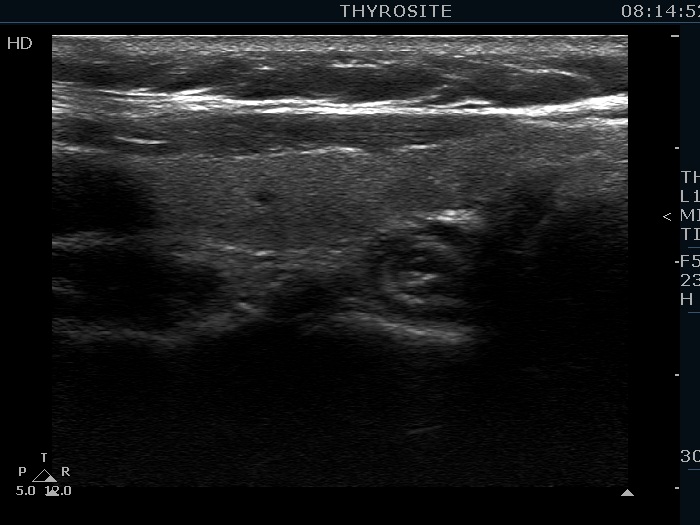

Ethanol sclerotherapy: toxic nodules - Case 2

Two years after repeated therapy (ultrasonographic picture 5)

Left lobe, longitudinal scan.